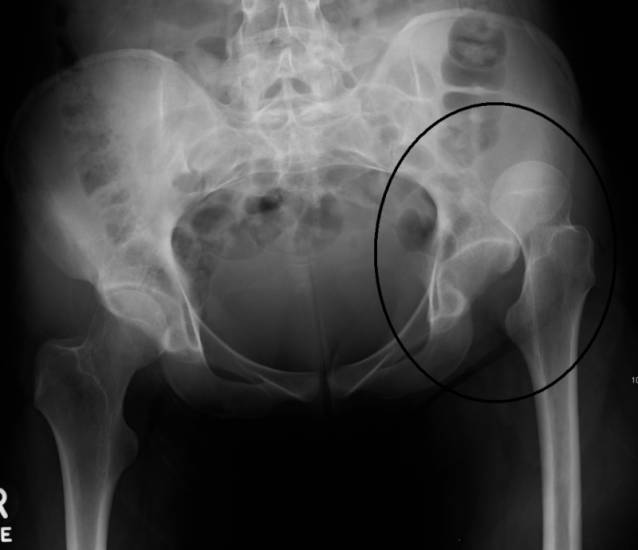

Вывих тазобедренного сустава имеет четко выраженные симптомы. Врачи утверждают, что при получении такой травмы спутать ее с каким-либо другим заболеванием практически нереально. Данную патологию обычно диагностируют без проведения дополнительных обследований. Некоторым пациентам для исключения наличия переломов тазобереднной кости может быть назначена рентгенография ТБС, которая проводится в двух проекциях. Также назначается МРТ в тех случаях, когда лечащие врачи имеют сомнения при определении точного диагноза.

Рентгенодиагностика является базовым методом определения подвывиха тазобедренного сустава у новорожденных. Возраст, когда ребенку нужно проводить рентгенодиагностику, окончательно не определен, но большинство врачей рекомендуют делать рентген после 3 месяцев жизни, поскольку до этого возраста большинство элементов еще сохраняют хрящевую структуру и не видны на рентгенограммах. Основным показанием, при котором рентгенограммы делают независимо от возраста, являются признаки подвывиха бедра.

Чтение и расшифровка рентгенограмм осуществляется врачом‐рентгенологом. При осмотре оценивают контур вертлужной впадины, расположение головки бедра. Основными ориентирами на рентгенограмме являются:

- Линия Шентона. Она проводится по медиальному (внутреннему) краю головки бедренной кости и переходит на верхний край лобковой кости. В норме линия имеет дугообразную форму, а при наличии патологии появляются изломы.

Линия Кальве. Проводится по наружному краю подвздошной кости таза с переходом на верхне‐наружный край головки бедра. В норме она также имеет дугообразную форму. При дисплазии ход линии приобретает изломы.

- Схема Хильгенрейнера‐Омбредана‐Перкенса. Она позволяет определить расположение головки бедра, на основании которой устанавливается диагноз. На рентгенограмме проводятся все основные ориентиры, описанные ранее. Далее от наружного края вертлужной впадины до бедра проводят вертикальную линию Омбредана, которая проходит через линию Хильгенрейнера до бедра. В результате тазобедренный сустав разделяется двумя взаимоперпендикулярными линиями на четыре части. В норме головка бедра должна находиться в верхнем внутреннем квадранте. При наличии патологии она смещена в наружные верхний или нижний квадрант.